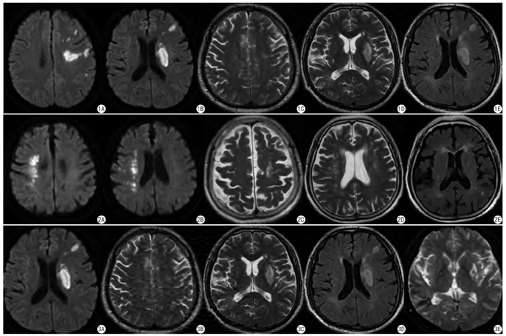

通过T1WI、T2WI及T2 FLAIR序列并根据下述标准对影像学改变进行评分。①血管周围间隙扩大:按照“中国脑小血管疾病共识”[9]中的定义来确定。对基底节及半卵圆中心区域EPVS分别计数评分[10]。0分:0个;1分:1~10个;2分:11~20个;3分:21~40个;4分:>40个。②脑白质高信号:分为侧脑室周围白质高信号(periventricular hyperintense,PVH)与深部白质高信号(deep white matter hyperintense,DWMH)。参照Fazekas等[11]的脑白质改变评分量表进行分级(0~3级)。③腔隙性脑梗死:也称腔隙灶,包括新发及陈旧性病灶。根据LI病灶的数目进行分级(0~ 3级)[12]。④微出血灶:结合DWI中b=0 s/mm2图像及T2WI像,表现为点状低信号而非连续≥2层出现视为微出血灶[13]。计数患者所有层面的微出血灶数量并分级(0~ 3级)[14]。⑤脑小血管病总体负担评分(total burden scores of CSVD,TBS):为统一评判患者CSVD的轻重程度,将同一患者的EPVS、WMH、LI及CMBs评分进行累加而获得TBS (0~ 4分)。具体评分方法如下[15]:有LI计1分;有深部微出血灶评计1分;DWMH 2~3分或PVH 3分计1分;中-重度基底节区扩大的血管周围间隙,即EPVS评分≥2分计TBS 1分。青年及老年急性脑梗死示例和CSVD相关评分见图1,图2,图3。

Kruskal-Wallis检验3组间CSVD各评分P<0.001 ,可以认为3组间CSVD评分差异具有统计学意义。经过两两比较,3组间患者TBS有显著差异(调整后P<0.001)。青年梗死组明显高于青年对照组,但显著低于老年组。

既往的一篇针对CSVD的神经影像学综述阐明,评估TBS是很有必要的[18]。Huijts等[19]首先应用此量表发现TBS与较差的认知功能相关。降钙素原水平升高[20]和门诊血压水平增高[21]也被确定与TBS呈正相关。本研究使用已建立的经过验证的量表对TBS进行分级,发现青年梗死组TBS明显高于青年对照组,但显著低于老年组,说明脑小血管病变在青年急性脑梗死患者中很常见。既往多针对单一脑小血管病特征进行研究,发现脑梗死患者多存在EPVS、LI、WMH、CMBs等[22,23],与本研究结果一致。